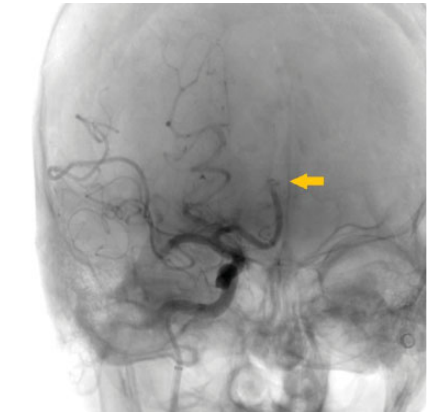

De nuestra serie de casos (n ¼ 228), solo se encontraron complicaciones en el 16,6%: hemorragias subaracnoideas secundarias a perforación (n ¼ 2) (►Fig. 1), hemorragia gangliobasal (n ¼ 1) (►Fig. 2), vasoespasmo (n ¼ 1), disección (n ¼ 1) (►Fig. 3), embolias (n ¼ 31) y pseudoaneurismas (n ¼ 2) (►Fig. 4) en el sitio de la punción. Cuando se detectó oclusión intracraneal (►Fig. 5), tras la trombectomía, dentro del grupo de las embolias, solo el 16,1% se presentaron hacia nuevo territorio vascular (arteria cerebral anterior) (►Fig. 6) o embolias distales. Debido al bajo número de complicaciones, se realizó un análisis mediante Fisher que da un resultado no significativo (►Tabla 3). Las hemorragias fueron subaracnoideas detectadas durante las trombectomías como la extravasación activa del contraste y corroborada mediante tomografía computada (TC) al finalizar el procedimiento. El vasoespasmo que se presentó fue moderado en arteria cerebral media izquierda que cedió tras la infusión intra-arterial de 0,2 mg nimodipino.

Arteriografía convencional. La flecha amarilla señala embolia postrombectomía en la ACM por fragmentación hacia el segmento A2 de la arteria cerebral anterior (ACA) ipsilateral, con restauración parcial del flujo a nivel de M1 del mismo lado.